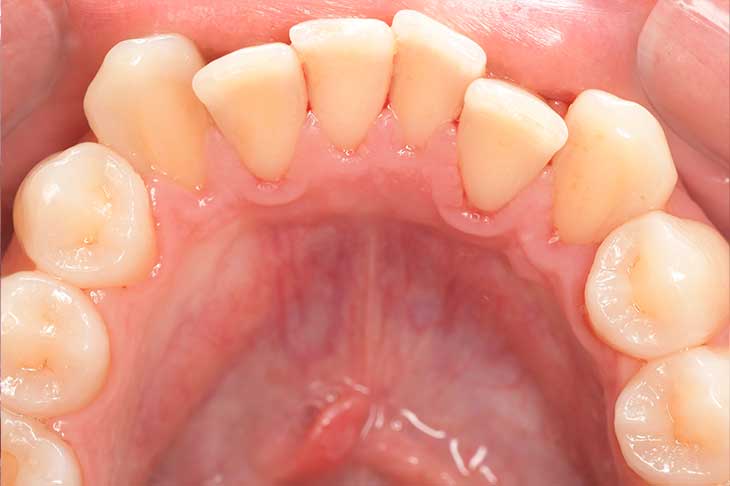

Before

After

基本情報

| 年齢・性別 | 52歳・女性 |

| 主訴 | クリーニングしたい |

| 治療内容 | スケーリング・PMTC |

| 治療期間 | 60分 |

| 治療費 | 約7,000円 |

| リスク・副作用 | 知覚過敏、歯肉退縮 |

| 治療方針 | 歯石とステインを除去して、今後は定期検診でのクリーニングと併せてガムピーリングやホワイトニングを行います。 |

| 担当者所見 | 歯肉の色素沈着が目立つため、ガムピーリングを行いながらホワイトニングを行うことをおすすめします。 |